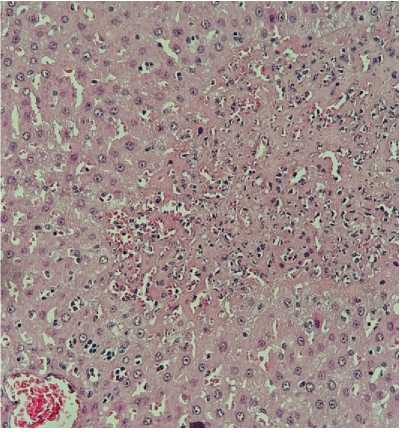

Рисунок 2. Гистологическая картина печени животных при проведении перфузии печени: А – перфузия раствором Кустодиола; В – перфузия раствором Кустодиол-М, умеренно выраженная дистрофия. Гематоксилин-эозин, ув. ×200

Figure 2. Histological appearance of animal liver during hepatic perfusion: A — perfusion with Custodiol solution; B — perfusion with Custodiol-M solution, moderately pronounced dystrophy. Hematoxylin-eosin staining, magnification ×200

Снижение активности АЛТ составило 76% (694 169 Ед/л, p<0,05) в группе MITOPERF и 55% (694 312 Ед/л, p<0,05) в группе Кустодиол-М по сравнению с контролем. Следует отметить умеренную межиндивидуальную вариабельность ответа (CV 35–54%), что отражает биологическую гетерогенность экспериментальной модели и является типичным для исследований на малых животных (рис. 1).

Полученные результаты демонстрируют, что экспериментальный раствор MITOPERF обеспечивает защиту печени от ишемически-реперфузионного повреждения при использовании в протоколе HOPE. Модифицированный раствор Кустодиол ex tempore обеспечивает промежуточный протективный эффект.